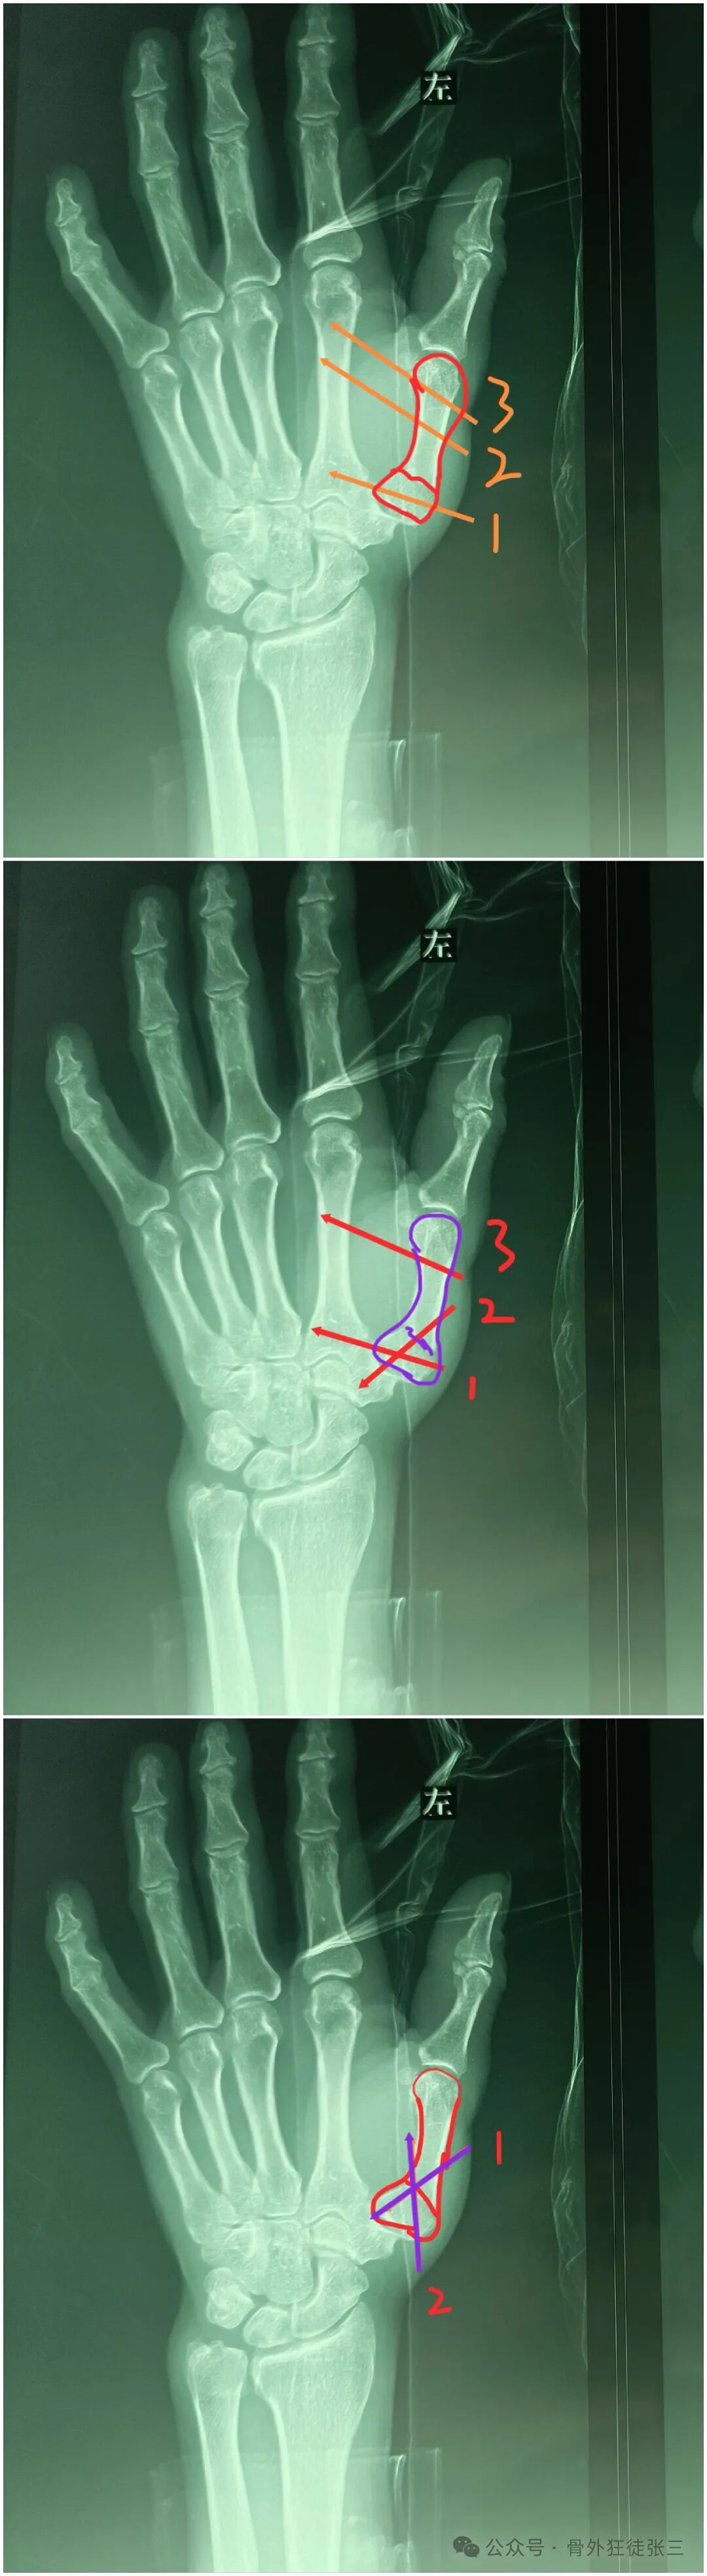

四、反Bennett骨折

病例7:

反Bennett骨折+第四掌骨骨折

闭合复位

“隔山打牛”

经皮穿针